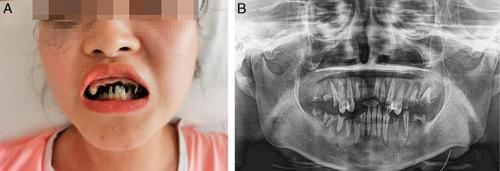

Here we report a case of Moyamoya syndrome associated with Graves' disease in a 19-year-old girl with sudden weakness of the right arm, progressive caries, and alopecia for 4 years. Brain magnetic resonance imaging revealed acute intraventricular hemorrhage and cerebral infarction of left middle cerebral artery territory and narrowing of the proximal portion of bilateral anterior and middle cerebral arteries.

Acute cerebral infarction and intraventricular hemorrhage can occur simultaneously in Moyamoya syndrome associated with Graves' disease. Hydrocortisone, combined with prothiouracil medication, can correct thyroid dysfunction and improve neurological function. Caries may be the first symptom of Graves' disease.

我们在此报告一例 19 岁女性患者,因右侧手臂突然无力、渐进性龋齿和脱发 4 年就诊,诊断为格雷夫斯病合并烟雾病。颅脑磁共振成像显示左侧大脑中动脉区域急性脑室出血和脑梗死,双侧大脑前动脉和大脑中动脉近端狭窄。

格雷夫斯病合并烟雾病可同时发生急性脑梗死和脑室出血。氢化可的松联合丙硫氧嘧啶治疗可纠正甲状腺功能障碍,改善神经功能。龋齿可能是格雷夫斯病的首发症状。